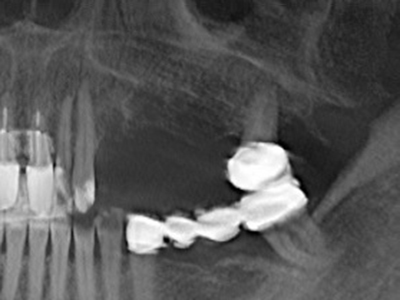

Bei der Knochenblockentnahme zeigen sich weitere Vorteile für die Piezochirurgie: Neben der bereits beschriebenen hohen Präzision bei der Osteotomie stellt sich gerade die Verwendung der dünnen Sägespitzen als besonders materialschonend heraus. Bei der Verwendung insbesondere von Lindemannfräsen sind mit deutlich höheren Entnahmeverlusten durch die dickere Instrumentenspitze zu rechnen (Lakshmiganthan, Gokulanathan et al. 2012). Die insbesondere bei retromolar entnommenen Blocktransplantaten notwendige basale Abtrennung wird durch speziell hierfür vorgesehene rechtwinklige Sägen erleichtert, so dass die Piezochirurgie als präzises, übersichtliches und sicheres Verfahren zur retromolaren Knochenblockgewinnung angesehen wird (Happe 2007) (Abb. 1-12).

Sollen chirurgische Eingriffe mit unmittelbarer Knochenbeziehung an empfindlichen Strukturen wie Blutgefäßen oder Nerven erfolgen, so bergen rotierende Instrumente ein erhebliches Potential an iatrogener Schädigung. Gerade bei Nervdarstellungen nach iatrogener Schädigung, oder aber im Zuge einer Nervlateralisation für resektive und rekonstruktive Eingriffe oder Implantatinsertionen können piezoelektronische Geräte hilfreich sein Knochendeckel zu präparieren und nervnahe Hartgewebsanteile zu entfernen (Abb. 17-20). Ein leichter Kontakt des Nervstrangs zur Piezospitze bleibt dabei in der Regel folgenlos – allerdings kann eine unvorsichtige Vorgehensweise mit sägeartigen Bewegungen bzw. Ansätzen bei noch vorhandener knöcherner Unterlage durchaus temporäre oder aber auch permanente Nervschädigungen verursachen. Das Risiko einer solchen Schädigung wird jedoch als wesentliche geringer eingeschätzt als unter Anwendung von Säge- oder Fräsinstrumenten (Pereira, Gealh et al. 2014).

Wie sich in der Vergangenheit gezeigt hat stellt prinzipiell jeder knochenchirurgische Eingriff eine mögliche Indikation für die Piezochirurgie dar. So lässt sich die Präparation des mobilen Segmentes bei der Distraktionsosteogenese (Abb. 23-25) und der Sandwichosteotomie mit speziellen Ansätzen bewerkstelligen, ohne die für den Erfolg beider Techniken essenzielle Blutversorgung des krestalen Anteils zu gefährden (Gonzalez-Garcia, Diniz-Freitas et al. 2008).